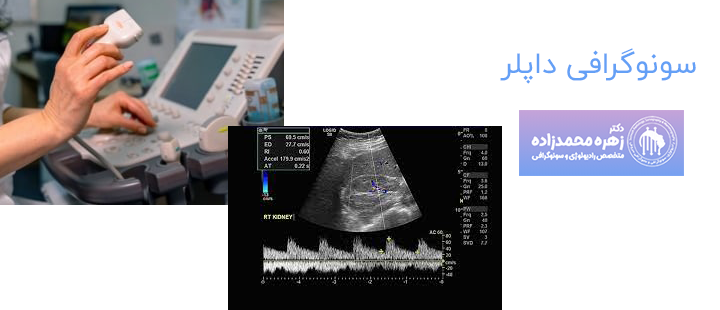

سونوگرافی داپلر یک روش تصویربرداری بوده که با استفاده از امواج صوتی حرکت خون در رگ های خونی را نشان میدهد. سونوگرافی داپلر بدون استفاده از اشعه ایکس یا هرگونه تزریق به پزشک کمک میکند تا آن چه درون رگ های بیمار در حال روی دادن است را مشاهده کرده و اطلاعات لازم را به دست بیاورند. سونوگرافی داپلر در مواردی برای اندازه گیری جریان و فشار خون نیز استفاده میشود.

در سونوگرافی داپلر پزشک با استفاده از ژل سونوگرافی و پروب سونوگرافی امواج صوتی را به بدن بیمار رسانده که حرکت سلول های خونی موجب تغییر در سطح امواج صوتی میشود. این امواج ضبط شده توسط دستگاه به تصاویر یا نمودارهایی تبدیل شده و روی مانیتور قابل مشاهده هستند. تقریبا انجام این سونوگرافی گاهی 30 الی 60 دقیقه طول میکشد.